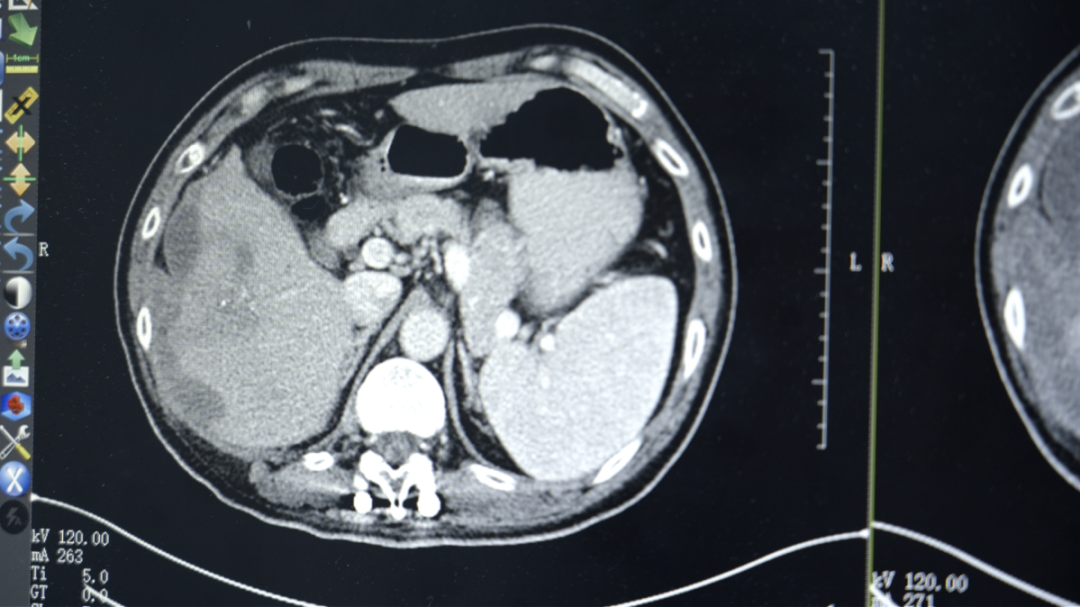

入院相关检查显示,勇哥的甲胎蛋白指标高达12.8万ng/ml(正常值<7ng/ml),肝功能评估为Child-Pugh B级(肝功能处于中度损害)。医疗六科李红梅主任团队根据他的具体情况,结合原发性肝癌CSCO指南,制定了靶向联合免疫的个性化治疗方案。

“吃了药,打了针,不怎么疼了,能吃饭能睡觉了。”几个疗程后,勇哥的生活质量明显改善。复查结果显示肿瘤得到控制,甲胎蛋白降至1.8万ng/ml。考虑到肝脏上病灶负荷太大,且紧靠周边,出血风险比较高,李红梅主任还是建议他进行肝动脉灌注化疗术(HAIC)。